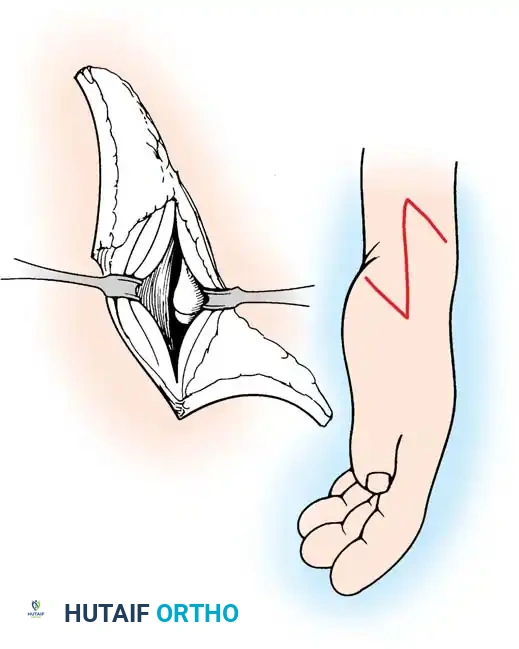

Surgical Interventions in Transverse Deficiencies

Surgical indications for transverse deficiencies are exceedingly rare. Epps, Burkhalter, and McCollough reported that out of 1,077 children